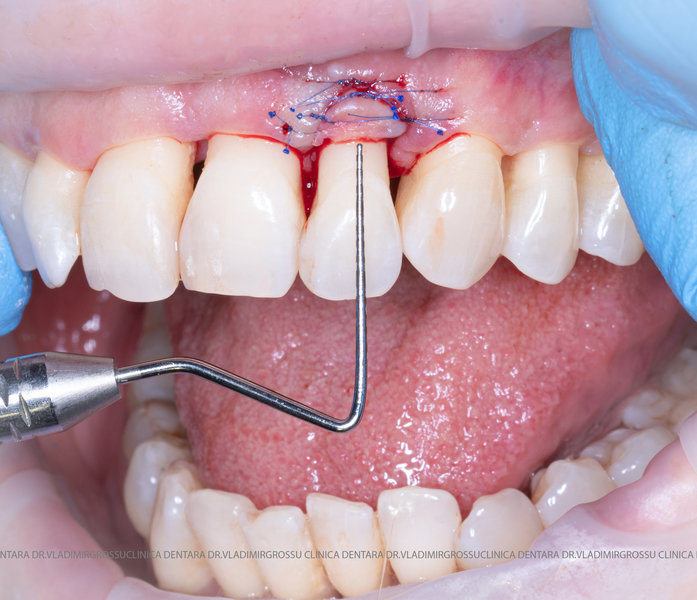

Aditia gingivală este o procedură chirurgicală ce corectează diverse probleme estetice și funcționale, cum ar fi recesiunea gingivală. În implantologia modernă, aditia de țesut moale este utilizată aproape în fiecare intervenție de inserție a implantului dentar pentru a asigura un aspect estetic natural și o bună integrare a implantului în cavitatea bucală.

Adiția osoasă are un rol crucial pentru poziționarea corectă și stabilă a implanturilor dentare. Clinica stomatologică Dr. Grossu din Chișinău promovează o abordare chirurgicală estetică și predictibilă, adaptată fiecărui caz în parte.

Medicii noștri au o vastă experiență atât în chirurgia estetică, cât și în protezarea cu un grad înalt de naturalitate, ceea ce ne permite să gestionăm cu succes și cele mai complexe cazuri.